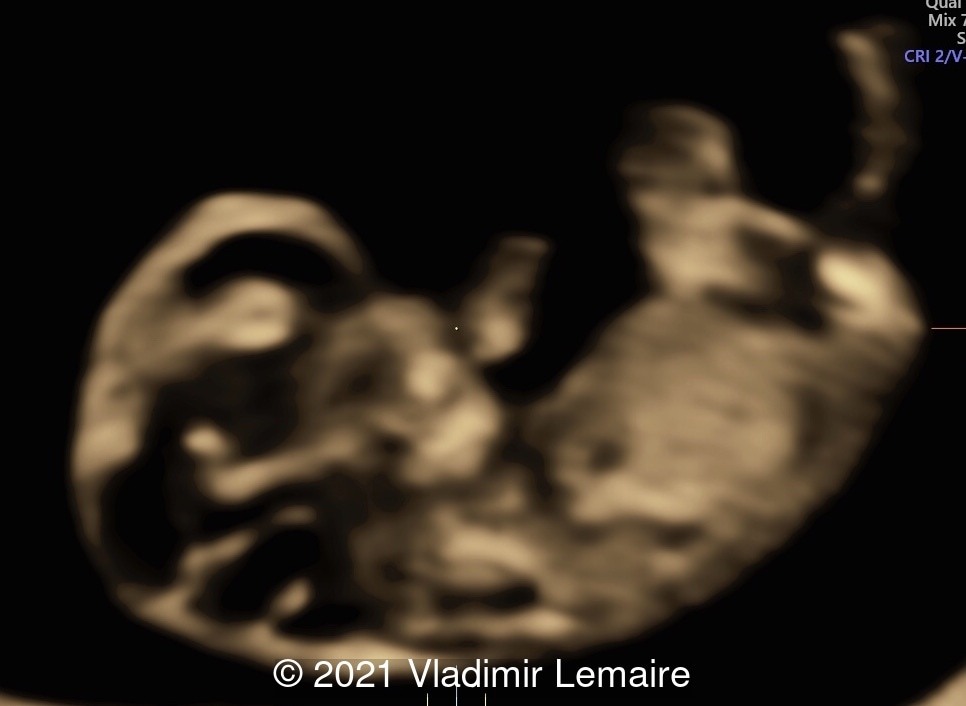

The following images demonstrate the normal appearance of the brain vesicles at 9 weeks of gestation.

At this point are easily identifiable: the telencephalon vesicles, the diencephalon, and the rhombencephalon.

Demonstration of early brain development using Volume Contrast Imaging (VCI) with 1-2 mm thickness. Note the development of the fourth ventricle at this gestational age. The choroid plexus of the fourth ventricle is also visible.